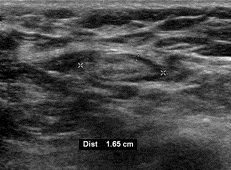

의료 초음파에서 B-모드 영상은 림프절 형태를 보여주며, 파워 도플러는 혈관 패턴을 평가할 수 있다.[28] 전이와 림프종을 구별할 수 있는 B-모드 영상 특징에는 크기, 모양, 석회화, 힐룸 구조의 소실, 림프절 내 괴사가 포함된다.[28] 연조직 부종과 B-모드 영상에서 림프절 유착은 결핵성 경부 림프절염 또는 이전 방사선 치료를 시사한다.[28] 림프절 크기와 혈관의 일련의 모니터링은 치료 반응을 평가하는 데 유용하다.[28]

의료 초음파에서 B-모드 영상은 림프절 형태를 보여주며, 파워 도플러는 혈관 패턴을 평가할 수 있다.[28] 전이와 림프종을 구별할 수 있는 B-모드 영상 특징에는 크기, 모양, 석회화, 힐룸 구조의 소실, 림프절 내 괴사가 포함된다.[28] 연조직 부종과 B-모드 영상에서 림프절 유착은 결핵성 경부 림프절염 또는 이전 방사선 치료를 시사한다.[28] 림프절 크기와 혈관을 일련으로 모니터링하는 것은 치료 반응을 평가하는 데 유용하다.[28]

1.5cm~2cm 이상의 림프절병증은 암 또는 육아종성 질환이 염증 또는 감염만 있는 경우보다 원인일 위험을 증가시킨다. 시간이 지남에 따라 크기가 증가하고 지속되는 것은 암을 더 시사한다.[39]